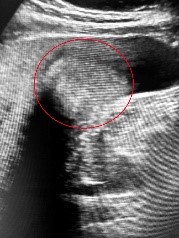

紅圈標示處為博田國際醫院肝膽胰外科副院長李金德教授為患者進行「膽囊附著處肝臟切除」及「膽管旁淋巴擴清術」手術部位示意圖